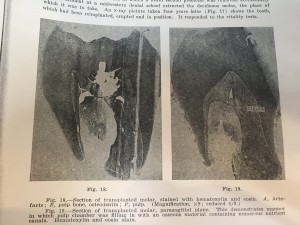

つまらないので、Histologic Investigationを読みます

移植後に第二象牙質が出来ている。

移植後に象牙細胞がちゃんと象牙質になるという証拠になってますとのこと。

あまりうまくいかないと、象牙質じゃなく、骨みたくなります

みたいなことが書いてあります。